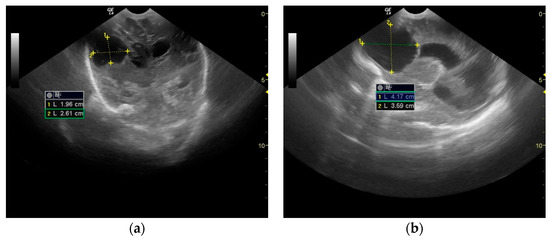

2. Case Presentation